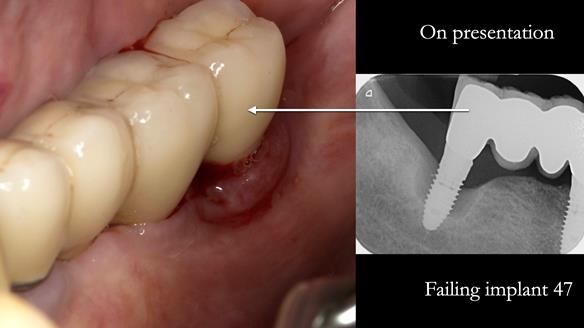

A posterior implant 47 had lost integration and was infected. This was removed.

Ken did not want further implant surgery.

Instead, we made a Scandinavian-style, metal-based lower RPD.